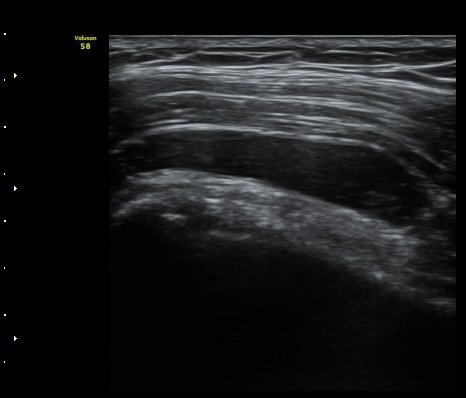

ÃÊÀ½ÆÄ °Ë»ç

¾î±ú À̵ιڱ٠Ⱦ´Ü¸é°Ë»ç¿¡¼­ ½ÉÇÑ Á¡¾×³¶³» ¼ö¾×Àú·ù°¡ °üÂûµÇÁö¸¸ ÆÄ¿öµµÇ÷¯

°Ë»ç¿¡¼­ Ç÷·ùÁõ°¡´Â °üÂûµÇÁö ¾Ê´Â´Ù(±×¸² 1, 2).   À̵ιڱ٠¾Æ·¡ Ⱦ´Ü¸é°Ë»ç¿¡¼­